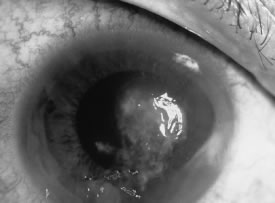

Candida infection typically produces epithelial ulceration, focal necrotizing stromal inflammation, moderate cellular infiltrate and edema in the adjacent stroma, and mild or moderate iritis in the early stages, indistinguishable from bacterial keratitis (Figs. 15, 16, and 17). Fungal elements cannot be detected by biomicroscopy. If untreated, the keratitis evolves to produce dense suppuration and necrosis of the deep stroma. Although multifocal suppuration may develop in polymicrobial keratitis, there is no distinctive sign of mixed Candida and bacterial infection (Fig. 18).

Fig. 15. C. albicans keratitis in an eye following chronic use of corticosteroid drops for herpes simplex keratitis. Note the central suppuration and perforation, endothelial plaques, and hypopyon.